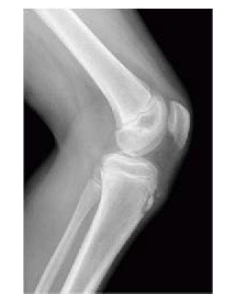

R.L.P, de 14 anos de idade, joga futebol diariamente com colegas de bairro, por ao menos quatro horas diárias. Iniciou, há cerca de um ano, com queixas de dor anterior em ambos os joelhos. Foi realizada a radiografia apresentada.

Com base nesse caso clínico e nos conhecimentos médicos correlatos, julgue os itens a seguir.